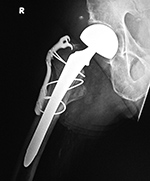

| Total hip arthroplasty with cerclage wires |

The cerclage wires were placed because a femoral shaft fracture (not visible herein) occurred during the prosthesis placement. There is subcutaneous gas from recent placement of the prosthesis. From Taljanovic, 2005 |